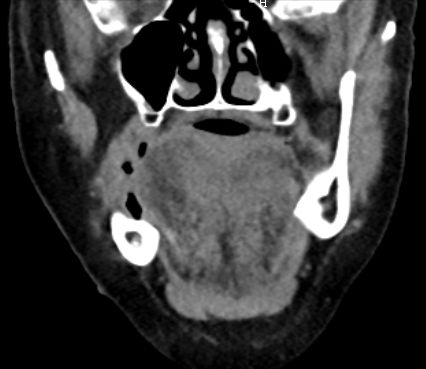

63-jähriger Mann mit Leberzirrhose und ACI-Stenose.

Es besteht ein Hypopharynx - Karzinom und ein Weichgaumenkarzinom mit Übergang auf den harten Gaumen.![]() | |||||||||||||||||